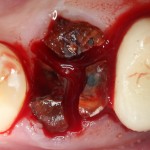

Начинаем с самого сложного — зуба #47:

Гранулема настолько большая, что ее видно из лунки:

Аккуратно ее удаляем. Приходится пожертвовать межкорневой перегородкой: